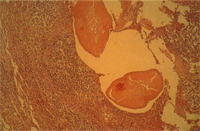

3. 肺:濕重潮紅,表面散發紅白相間之大理石花紋樣結構。 4. 肝:全面腫大鬱血(圖3),呈紅白相間樣,且充滿大量血液(圖4)。

4. 肝:嚴重鬱血及典型荳蔻肝病變,門脈區及中心靜脈區之結締組織增生,肝小葉周圍細胞壞死及顯著充出血。 5. 腎:皮質部充出血,髓質部鬱血,間質性腎炎。 6. 脾及淋巴結:嚴重鬱血,且有大量血鐵素沈著。 四 、